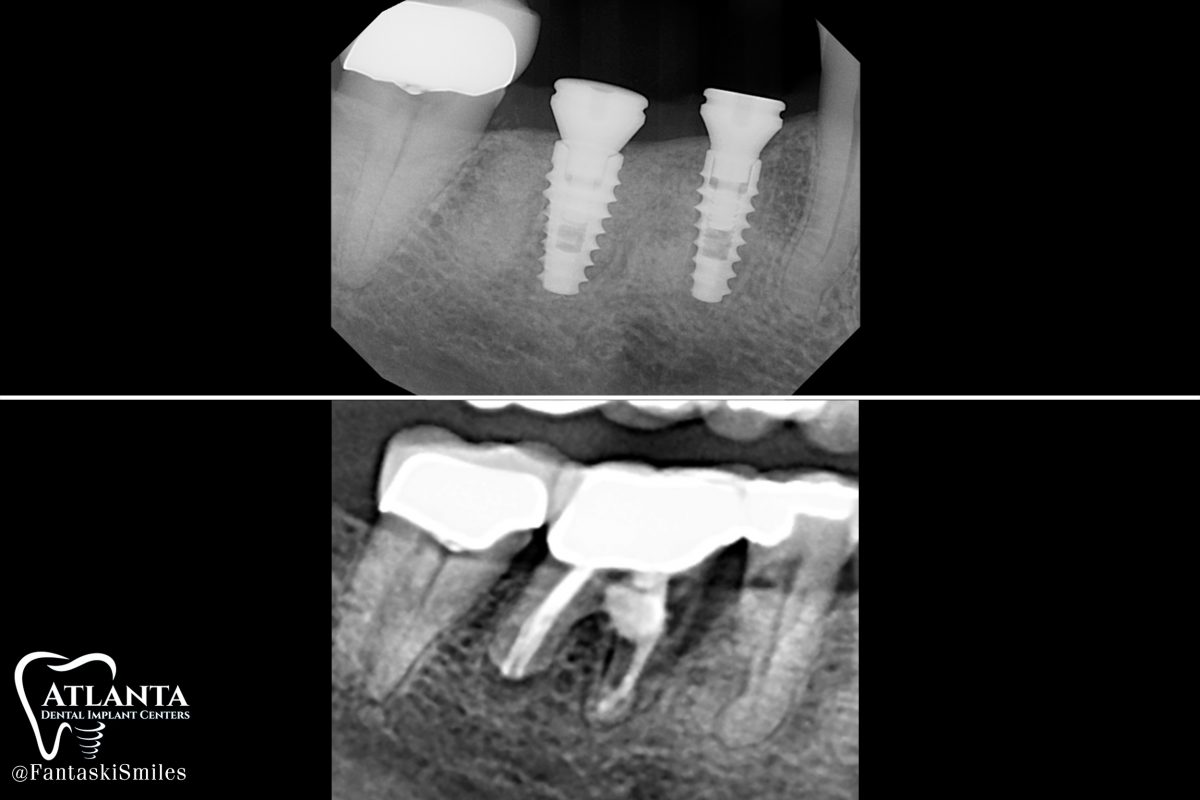

https://drfantaski.com/wp-content/uploads/2023/02/RB_Implant_xrays-1200x800.jpg